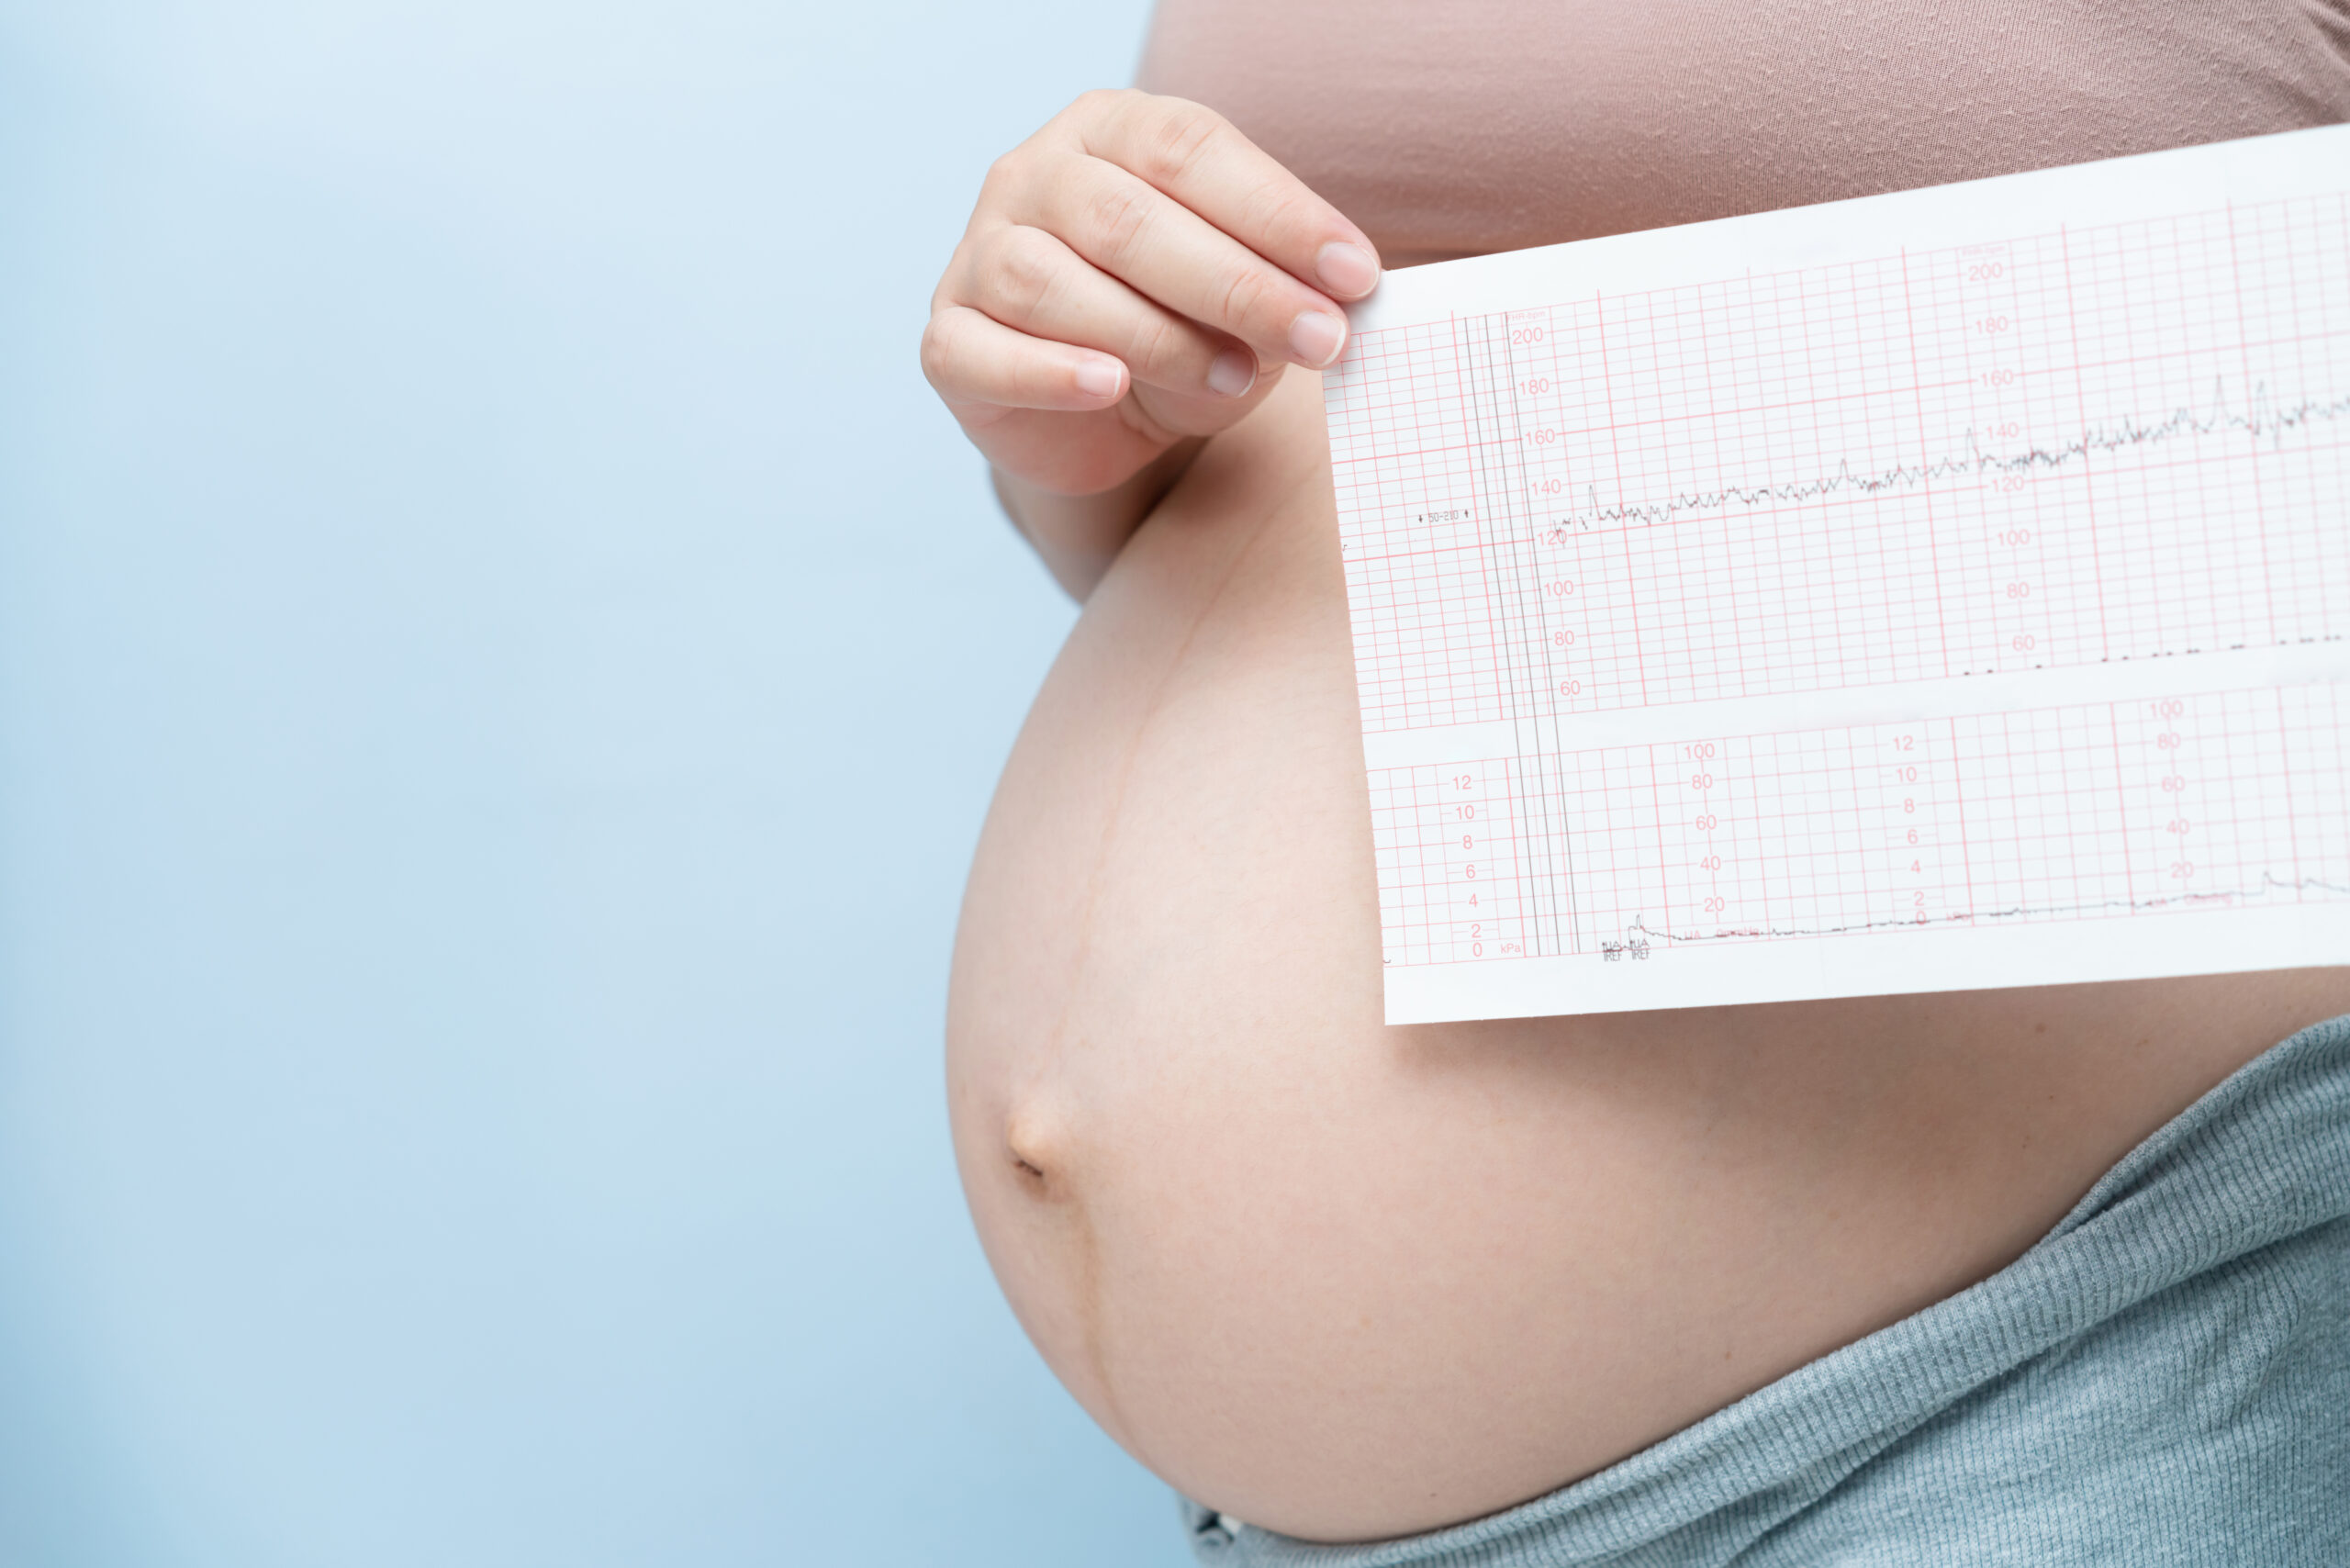

3. Trimenon

Diese Schwangerschaftsphase ist geprägt von intensiven Veränderungen und Vorbereitungen für die Geburt. Der wachsende Bauch und das erhöhte Gewicht können körperliche Beschwerden verursachen. Die Vorsorgeuntersuchungen mit zusätzlicher Kardiotokographie / CTG sollen sicherstellen, dass Mutter und Kind optimal versorgt werden.